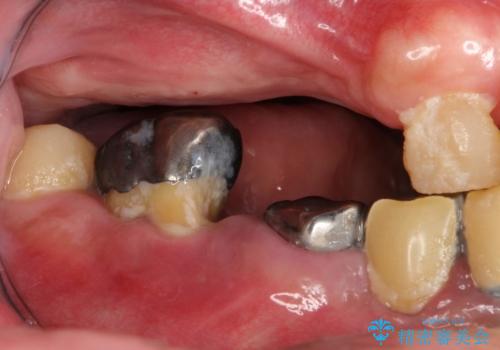

虫歯だらけ、歯周病 崩壊した口腔の再建 フルマウスリコンストラクション

- 歯周外科・インプラント・顕微鏡下根管治療などを含んだ総合的な治療を計画した。

かみ合わせの力が非常に強く、夜間の歯ぎしり・食いしばりもひどかったため、奥歯はメタルオクルーザルの設計でかぶせ物を製作しています。